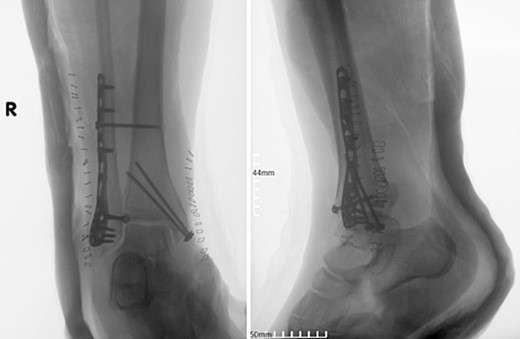

A 55-year-old female patient was admitted to the emergency department of our hospital due to an inability of weight bearing following a fall from standing height. Her medical history was unremarkable, with no significant records or regular medication use. Radiological evaluation revealed a trimalleolar fracture of the right ankle. Consequently, a cast was applied for pain management, and no weight-bearing was allowed on the affected limb (Fig. 1).

Anteroposterior and lateral X-ray of the ankle joint showing the trimalleolar fracture.